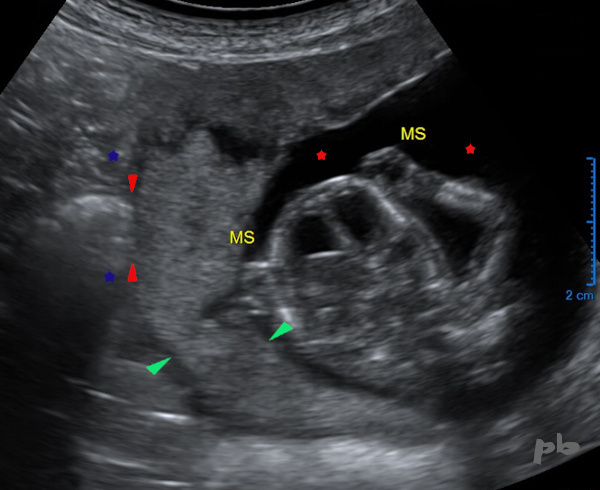

42 – Grossesse abdominale

1ère échographie à 13 SA.

Pas d’anomalie visualisée.

-MS = membres supérieurs. La tête au milieu.

-Liquide amniotique (

)

-Placenta (

Le tube digestif maternel (

) est directement au contact de l’œuf, sans interposition de tissu utérin (

).

Le diagnostic de grossesse abdominale ne sera porté finalement qu’un mois plus tard.

La localisation extra-utérine aurait été plus facilement retrouvée sur une échographie précoce.

42 – Abdominal pregnancy

First ultrasound at 13 weeks of gestation. No visible abnormalities.

MS = upper limbs. The head is in the middle.

Amniotic fluid (★)

Placenta (►)

The maternal digestive tract (★) is directly in contact with the egg, without interposition of uterine tissue (►).

The diagnosis of abdominal pregnancy will finally be made only a month later. The extrauterine location could have been more easily found on an early ultrasound.